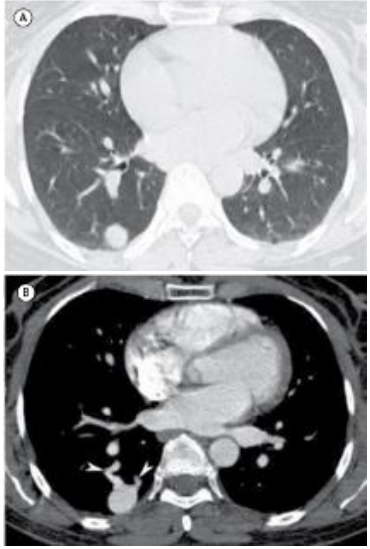

Mulher, 37 anos, queixando-se de tosse e febre há três dias. A paciente realizou tomografia computadorizada como parte da rotina diagnóstica.

Em relação ao exame apresentado, assinale a afirmativa correta.